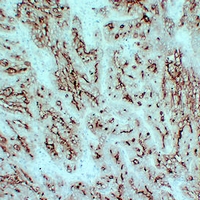

IHC (Immunohistochemistry)

(Immunohistochemical analysis of CD66e staining in human tonsil formalin fixed paraffin embedded tissue section. The section was pre-treated using heat mediated antigen retrieval with sodium citrate buffer (pH 6.0). The section was then incubated with the antibody at room temperature and detected using an HRP conjugated compact polymer system. DAB was used as the chromogen. The section was then counterstained with haematoxylin and mounted with DPX.)